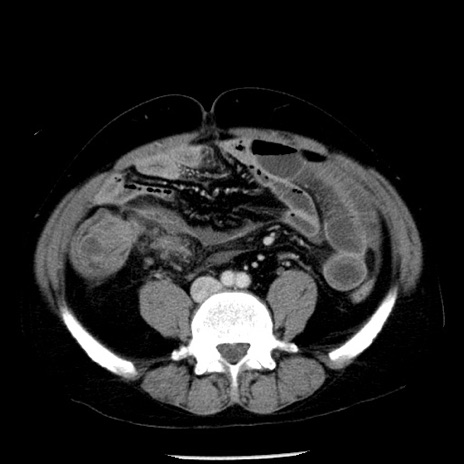

冠状断像

【症例】40歳代男性

【現病歴】2日前から胃痛あり。徐々に周期的な激痛に変化した。本日になっても激痛があるため受診。

【身体所見】意識清明、BT 38-39℃台あり、腹部:膨満、やや硬、右下腹部に圧痛あり。

【データ】WBC 8500、CRP 23.26